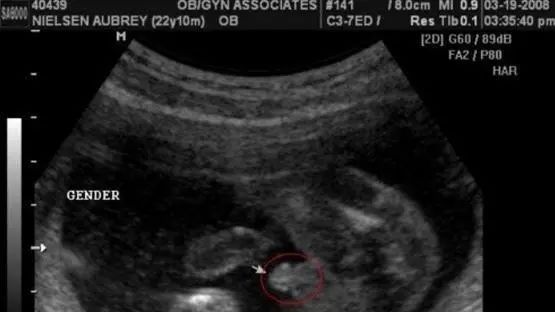

在怀孕到一定阶段的时候,在做b超的时候是可以看到孕囊的,在5周左右基本可以看见,但是此时很小,对于大家说的孕囊形状看男女究竟是怎么看呢,孕囊是有它的形状的,在观察孕囊的形状,如果发现是长条状的话,则可能是男宝宝,如果孕囊的形状是椭圆形或者圆形的话,则可能是女宝宝哦。

孕囊要看早期形状,40-50天左右是最准的,如果是9周以后的数据准确性就很低了。